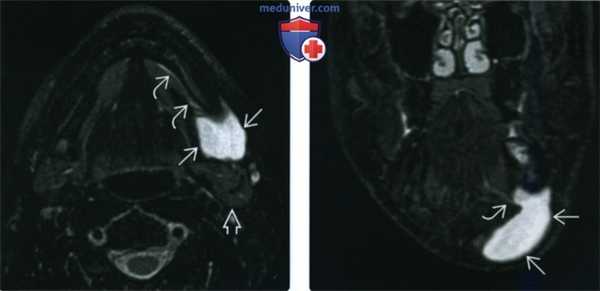

(Слева) МРТ Т2ВИ FS, подросток с рецидивирующей припухлостью в поднижнечелюстной области. В прошлом пациенту дважды выполнялась аспирация содержимого кисты. Определяется образование В с четкими контурами и гиперинтенсивным сигналом, которое находится кпереди от поднижнечелюстной железы и латеральнее челюстно-подъязычной мышцы. Признак «хвоста» лучше всего виден на Т2ВИ.

(Справа) МРТ Т2ВИ FS, коронарная проекция. Латеральная погружная ранула, которая представляет собой крупное кистозное образование поднижнечелюстного пространства. Часть ранулы (признак «хвоста») проходит через дефект в челюстно-подъязычной мышце.

(Слева) На аксиальной МРТ (Т2 ВИ FS) у молодого взрослого с рецидивирующим образованием в поднижнечелюстной области, дважды перенесшего аспирацию содержимого кисты, спереди от ПНЖ В и снаружи от челюстно-подъязычной мышцы визуализируется образование с четкими контурами и крайне высокой интенсивностью сигнала Т2 FS лучше всего позволяет оценить едва различимый симптом «хвоста» (признак более редкой боковой HP).

(Справа) На корональной MPT (Т2 ВИ FS) у этого же пациента определяется боковая HP в виде большого кистозного образования в ПНП с едва различимым «хвостом», проникающим через дефект челюстно-подъязычной мышцы.